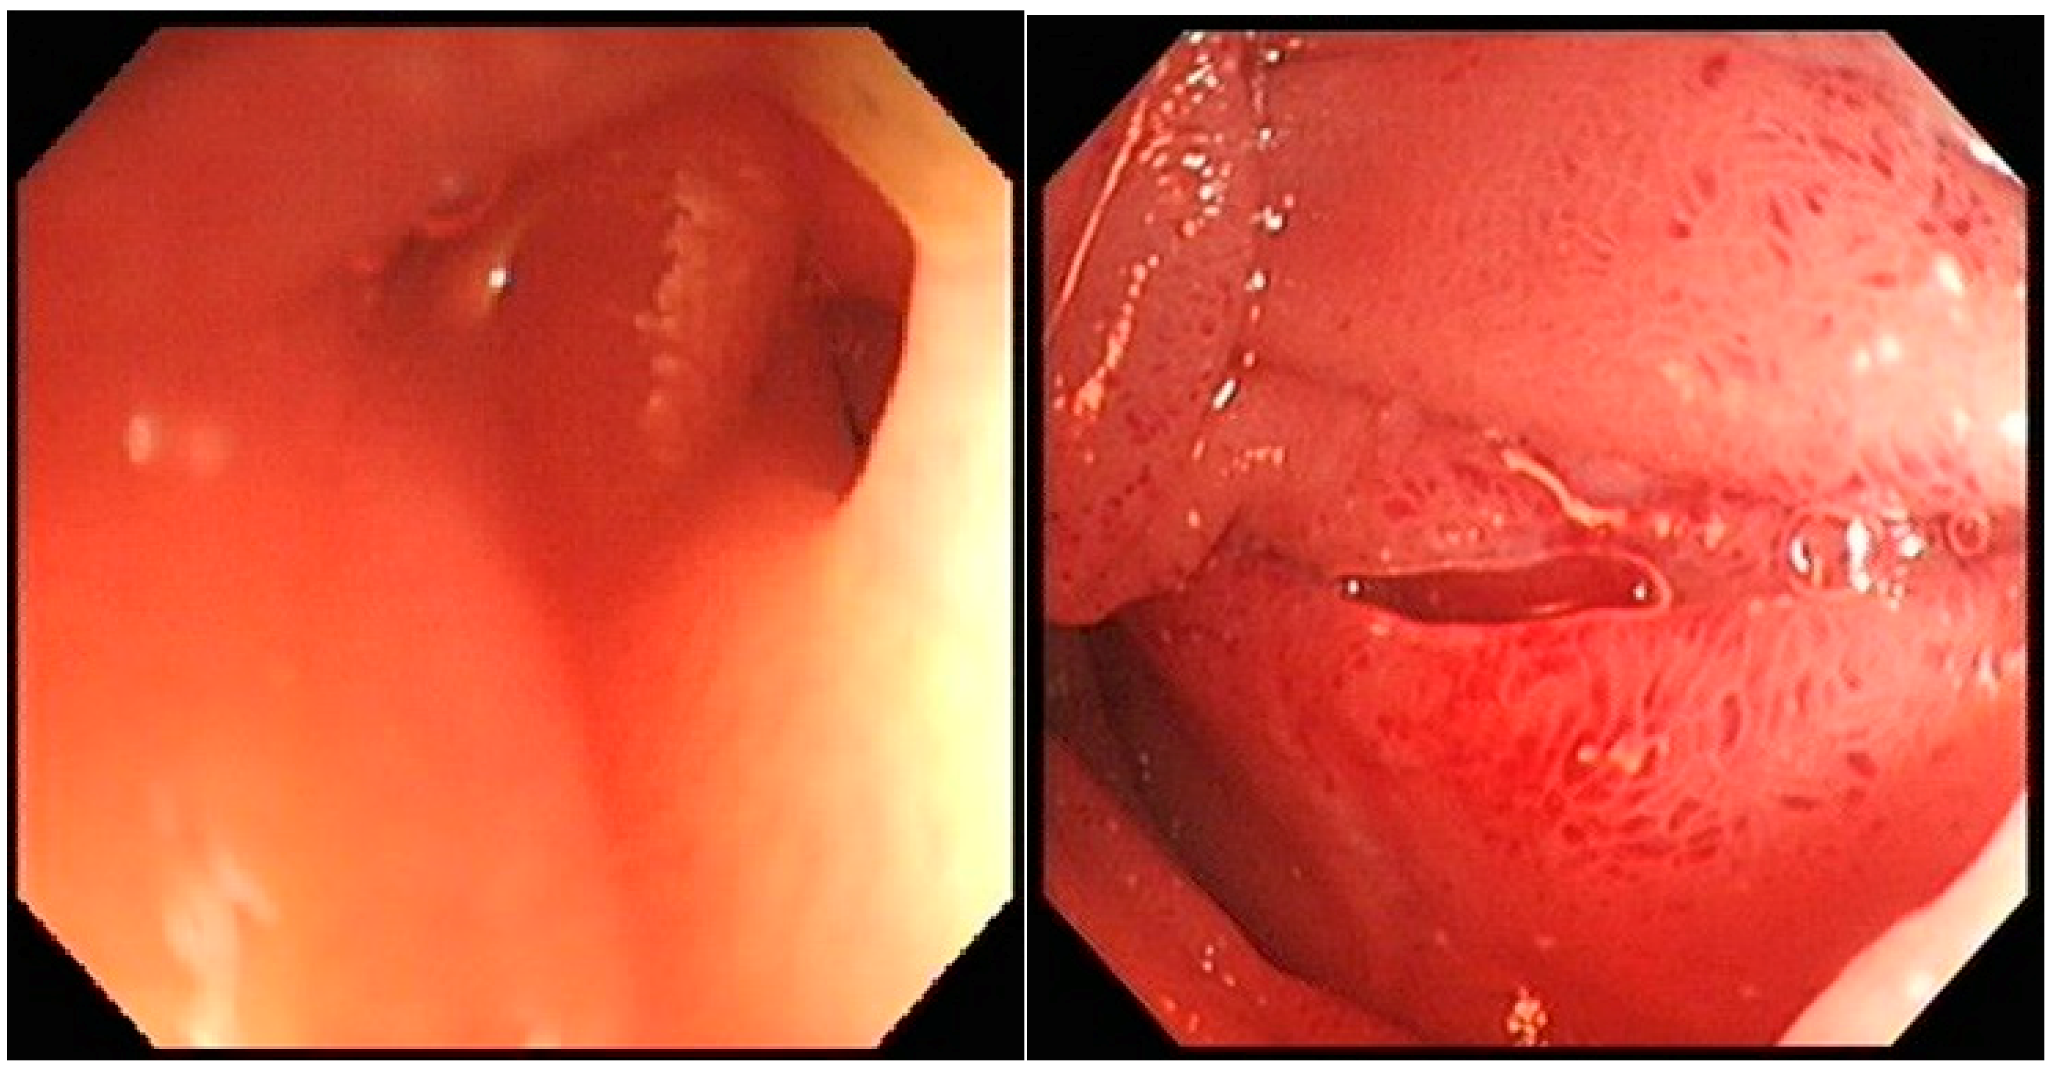

Repeat inpatient OGD was challenging as there was extrinsic compression in the area of third part of the duodenum (D3), preventing further passage of the endoscope, Figure 1.

OGD images showing partial obstruction in the third part of the duodenum (D3) preventing the passage of the endoscope.